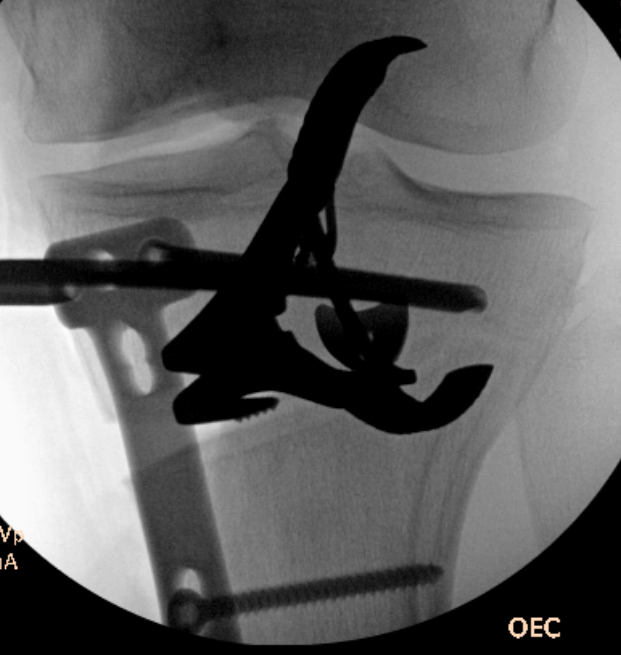

Check correct alignment with drop rod

- goal lateral tibial spine

- Fujisawa point / 62% of the tibial plateau / lateral tibial spine